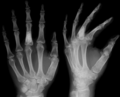

On radiographs, streaks of low density are seen projecting through the diaphyses into the epiphyses of the long bones, due to ectopic cartilage deposits. With age, the cartilage may calcify in the typical "snowflake" pattern.

X-ray showing calcified enchondromas localized in finger a 37-year-old patient affected with Ollier disease